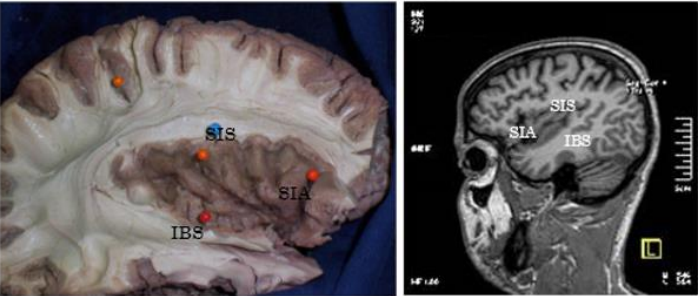

Usually the insula is triangular in shape with an anterior base. It is limited by three sulcus: the anterior insular sulcus (AIS), the superior insular sulcus (SIS), and the inferior insular sulcus (SII)1.

The SIA measured an average of 24mm, the SIS had an average of 52mm, and the SII measured an average of 47mm (Figure 2 and 3).

Figure 2 and 3: vision in anatomical preparation and in MRI of the insula, with its SIA, SIS, and SII.